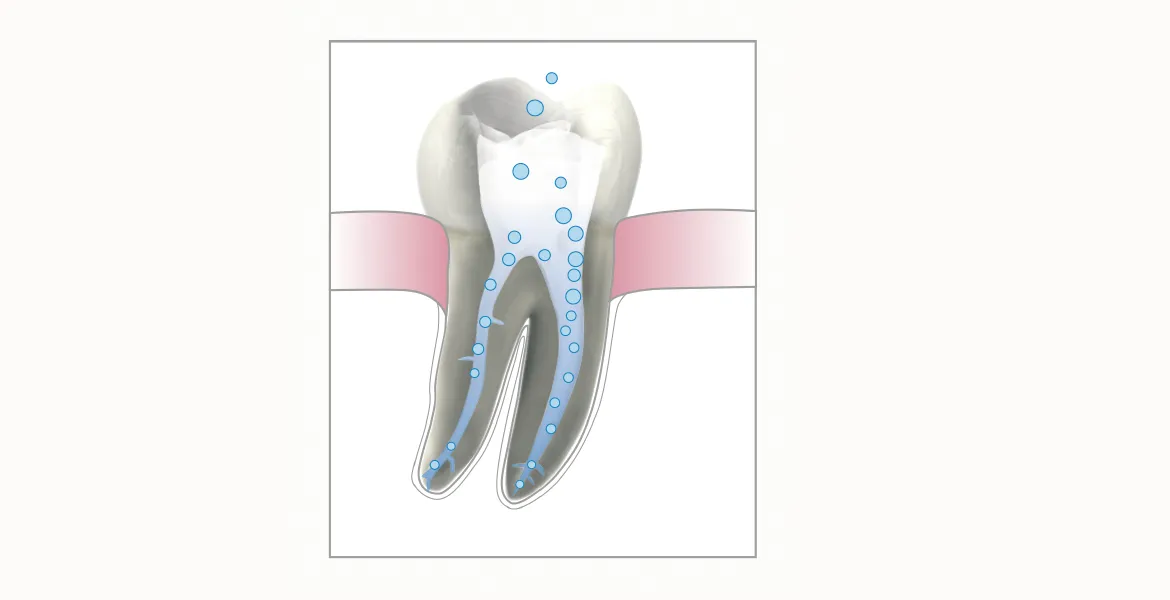

Die Wurzelbehandlung (Endodontie) ist meist ein technisch sehr anspruchsvoller Eingriff, um einen stark zerstörten Zahn zu erhalten. Diese Behandlung kann bei Entzündungen, Vereiterungen oder Nekrosen erforderlich werden. Das Ziel ist die vollständige Entfernung der geschädigten Zahnsubstanz und die innere Reinigung des Zahnes mit anschließender dichter Füllung. Dabei erhöhen moderne Aufbereitungs-, Reinigungs-, Diagnose- und Spülverfahren die Erfolgswahrscheinlichkeit erheblich. Je nach Zahnsituation sind unterschiedliche Verfahren Materialien sinnvoll und können bei uns durchgeführt werden.